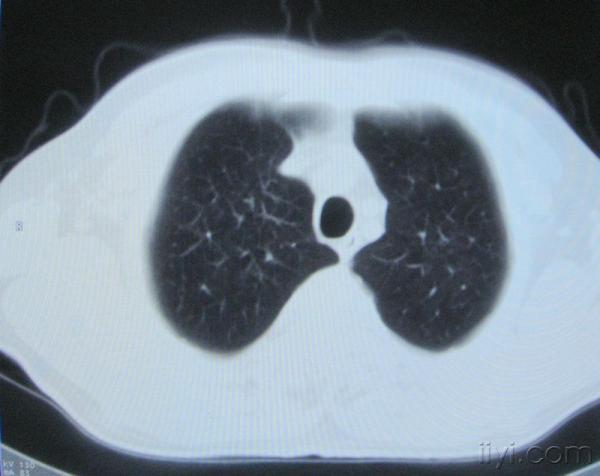

男。60岁,胸片示支气管炎治疗后复查CT。

应该是淋巴结没问题的,中心液化坏死是有这种情况的~~胸科常见到